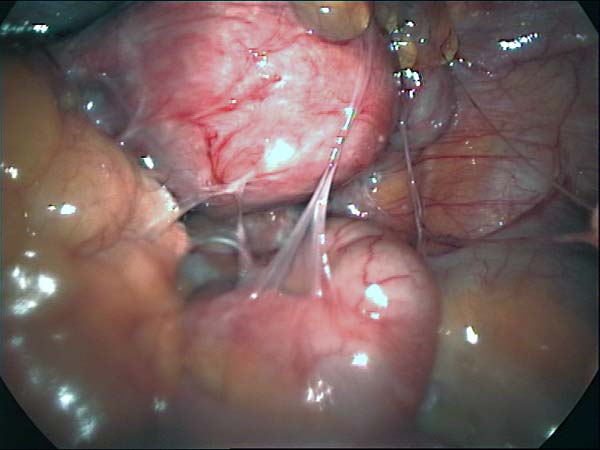

Laparoscopy Photos Ovarian Cyst Ovarian Cystectomy Uterine Septum Tubal Pregnancy